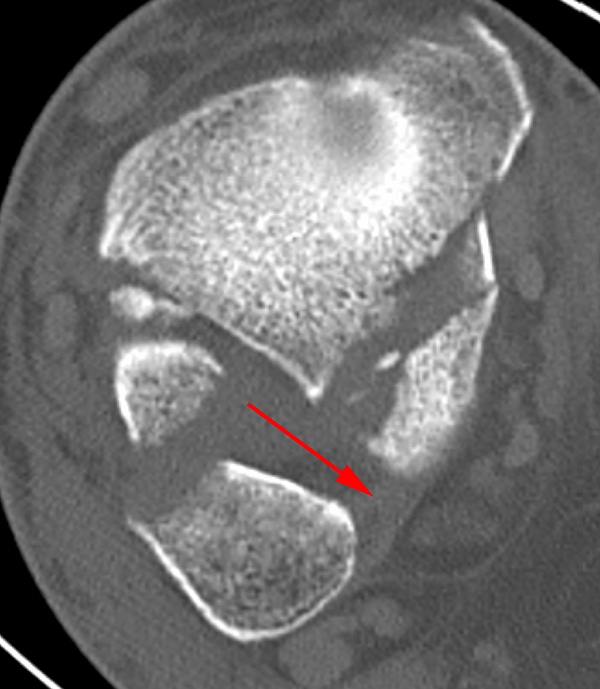

Seit einer Untersuchung von Nelson und Jensen aus dem Jahre 1940 wird allgemein akzeptiert, dass die Indikation zur Osteosynthese des Tibiahinterkantenfragments nur dann besteht, wenn die Größe mehr als ein Drittel (nach zahlreichen Autoren auch ein Viertel) der Gelenkfläche beträgt (Abbildung 15) 25. Dieses bis heute allgemeinakzeptierte Vorgehen basiert auf der Beobachtung von lediglich acht unterschiedlich versorgten Patienten. Seither gibt es keine weiteren klinischen Studien, die dieses Vorgehen stützen. Mittlerweile gibt es allerdings zunehmend Hinweise, dass bei der Versorgung des posterioren Malleolus viele andere Faktoren eine wichtige Rolle spielen 26. Da an der Tibiahinterkante das Lig. tibiofibulare posterius ansetzt (Abbildung 16), wird durch die offene Reposition und Stabilisierung die Integrität und die physiologische Spannung der hinteren Syndesmose rekonstruiert (Abbildung 17). Dies ist entscheidend für die anatomische Reposition der Fibula in der Tibiainzisur.

Gardner et al. konnten beispielsweise zeigen, dass die offene anatomische Reposition der Tibiahinterkante der Stabilisierung mittels Stellschraube überlegen war und gleichzeitig mit einer geringeren Rate an postoperativen Fehlstellungen der Fibula in der CT-Kontrolle einherging 2728. Aus Sicht der Autoren ist prinzipiell die Stabilisierung über eine direkte Reposition indiziert, wenn die Größe des Fragmentes dies erlaubt. Bei gleichzeitigem Vorliegen einer Fraktur des lateralen und/oder medialen Malleolus sollte zunächst die Versorgung der des Tibiahinterkantenfragments erfolgen. Dies erlaubt die radiologische Kontrolle der Reposition und Osteosynthese-Lage, welche durch eine zuvor aufgebrachte Fibula-Platte häufig erschwert ist 29. Dafür werden die Patienten in Seitenlage gelagert. Dies erlaubt die direkte Versorgung der posterioren Malleolusfraktur über einen posterolateralen Zugang 30. Das sehr kräftige Periost wird im Frakturverlauf inzidiert und aus den Frakturspalt entfernt, so kann eine anatomische Reposition erfolgen. Entsprechend der Fragmentgröße erfolgt entweder die Versorgung mittels Drittelrohrplatte in Antiglide-Technik oder eine Zugschraubenosteosynthese. Die Versorgung der Fibula-Fraktur gelingt über den gleichen Zugang. Zur Versorgung des medialen Malleolus wird der Patient auf den Rücken umgelagert. Dies kann bei entsprechender Vorbereitung ohne erneutes steriles Abdecken erfolgen. Durch dieses Vorgehen konnte im eigenen Kollektiv die Notwendigkeit einer Stabilisierung der Syndesmose mit Stellschraube/Tight Rope deutlich reduziert werden.